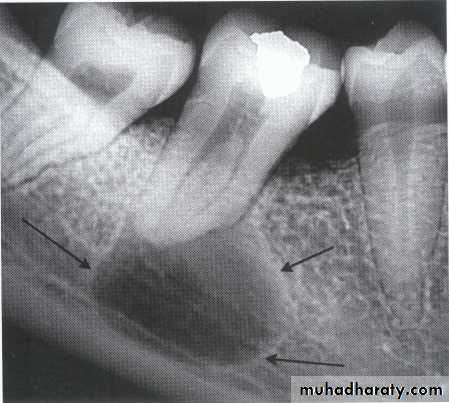

Multilocular appearance, expansion (arrowed) and considerable displacement of the adjacent teeth.

Buccal and lingual expansion (arrowed) and the undulating cortical border.

Large multilocular aneurysmal bone cyst

in the ramus with marked expansion andthe displacement of/8.

It is non-neoplastic ,exaggerated , localized, proliferative lesion of vascular tissue, containing giant cells.

It’s a variation of the central giant cell granuloma , can be diagnosed only by histological examination